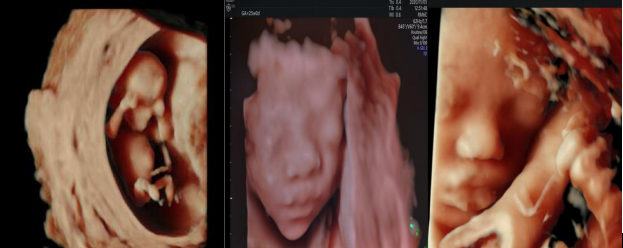

世界顶级四维彩超机美国 GE Voluson E10 BT20金标版落户我院

煊影成像技术:使三维图像更加逼真(早、中、晚孕期)

四维超声模式下输出功率指数与二维超声模式下相同,对胎儿无任何伤害

近日,我市首台全球顶级四维彩超机落户吉林省吉林中西医结合医院电诊科,目前经过调试已正式投入使用。

一台专业优秀的妇产超声机,对于产前胎儿四维超声筛查、子宫双侧附件及女性盆底功能障碍性疾病检查需要具备高端专业的处理机制。GE Voluson E10 BT20金标版在原有高端平台的基础上搭载了全新的煊光成像平台、煊影成像技术和煊流成像技术,能够360°高清立体、超真动态地显示宝宝的实时活动图像,创新性的二维立体血流成像模式Radiant flow、超低速血流成像模式 SlowflowHD,即便是微小的血管也能轻松的快速显现,提高了血流的视觉敏感性,卓越的图像质量,大大提高了临床诊断的准确率。

吉林省吉林中西医结合医院电诊科拥有世界一流的设备,无论是胎儿四维检查、妇科超声以及盆底超声检查较以前图像更清晰,成像效果更注重细节处理,可以更好的呈现解剖细节信息,尤其适用于较小的细微结构显示及运动状态显示,加之电诊科高素质的专业医疗团队,将为江城百姓提供最优质的诊疗服务!